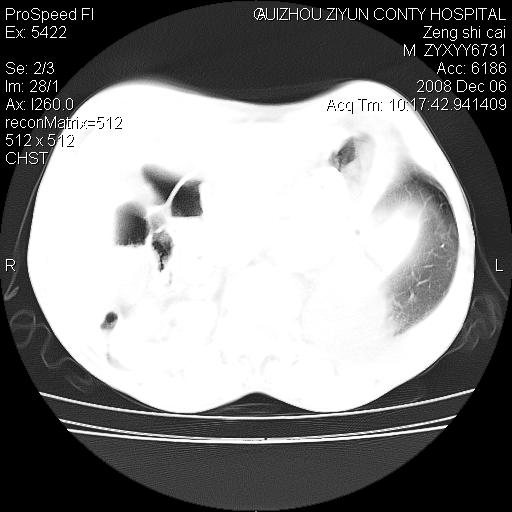

标题: CT16961:M、71岁,咳嗽半年,无血痰;胸片示右肺占位。 [打印本页]

标题: CT16961:M、71岁,咳嗽半年,无血痰;胸片示右肺占位。

1)考虑右肺上叶纵隔型肺癌伴纵隔淋巴结转移。2)心包积液,双侧胸腔积液。

右肺上叶纵隔型肺癌伴纵隔淋巴结转移。心包积液,双侧胸腔积液。

建议强化!主要鉴别是淋巴瘤与肺癌淋巴结转移。